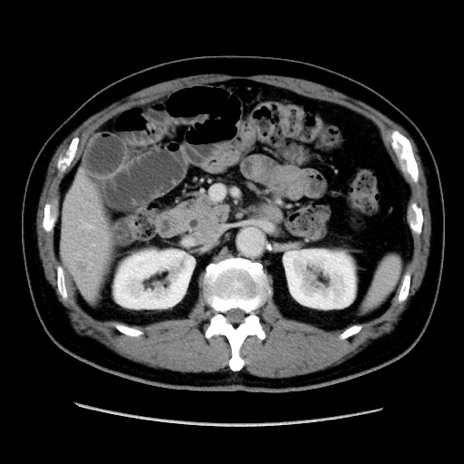

症例16(横断像)

【症例】 70歳代男性

【主訴】 腹痛、嘔吐

【現病歴】 約1ヶ月前より間欠的に腹痛と嘔吐あり、当院消化器内科を受診したところCTで多発する肝臓のLDAを指摘され、精査中であった。以降は消化器症状は安定していたが、2日前より嘔気と腹痛があり、同日より排便・排ガスが消失した。改善認めず、 本日、救急外来を受診した。

【既往歴】 大腸ポリープ切除後。

【身体所見】意識清明・会話良好、BT 36.3℃、BP 127/80mmHg、 P 80bpm、腹部:膨満あり、平坦・軟、上腹部正中および下腹部正中に圧痛あり、反跳痛なし、筋性防御なし。

【データ】WBC 7200、CRP 0.77